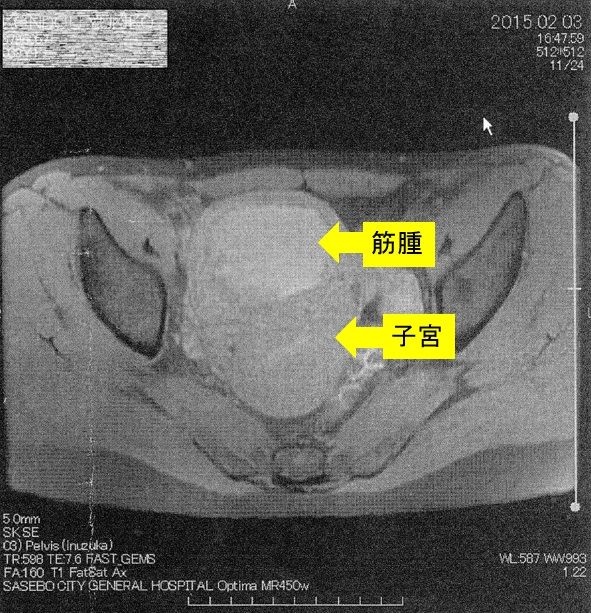

¡Ú2015ǯ2·î3Æü¡¡£Í£Ò£É¼Ì¿¿¡Û

¢¨Çò¤¤Éôʬ¤¬¶Ú¼ð¡¢¼þ¤ê¤ÎÉôʬ¤¬»ÒµÜ¤Ç¤¹¡£